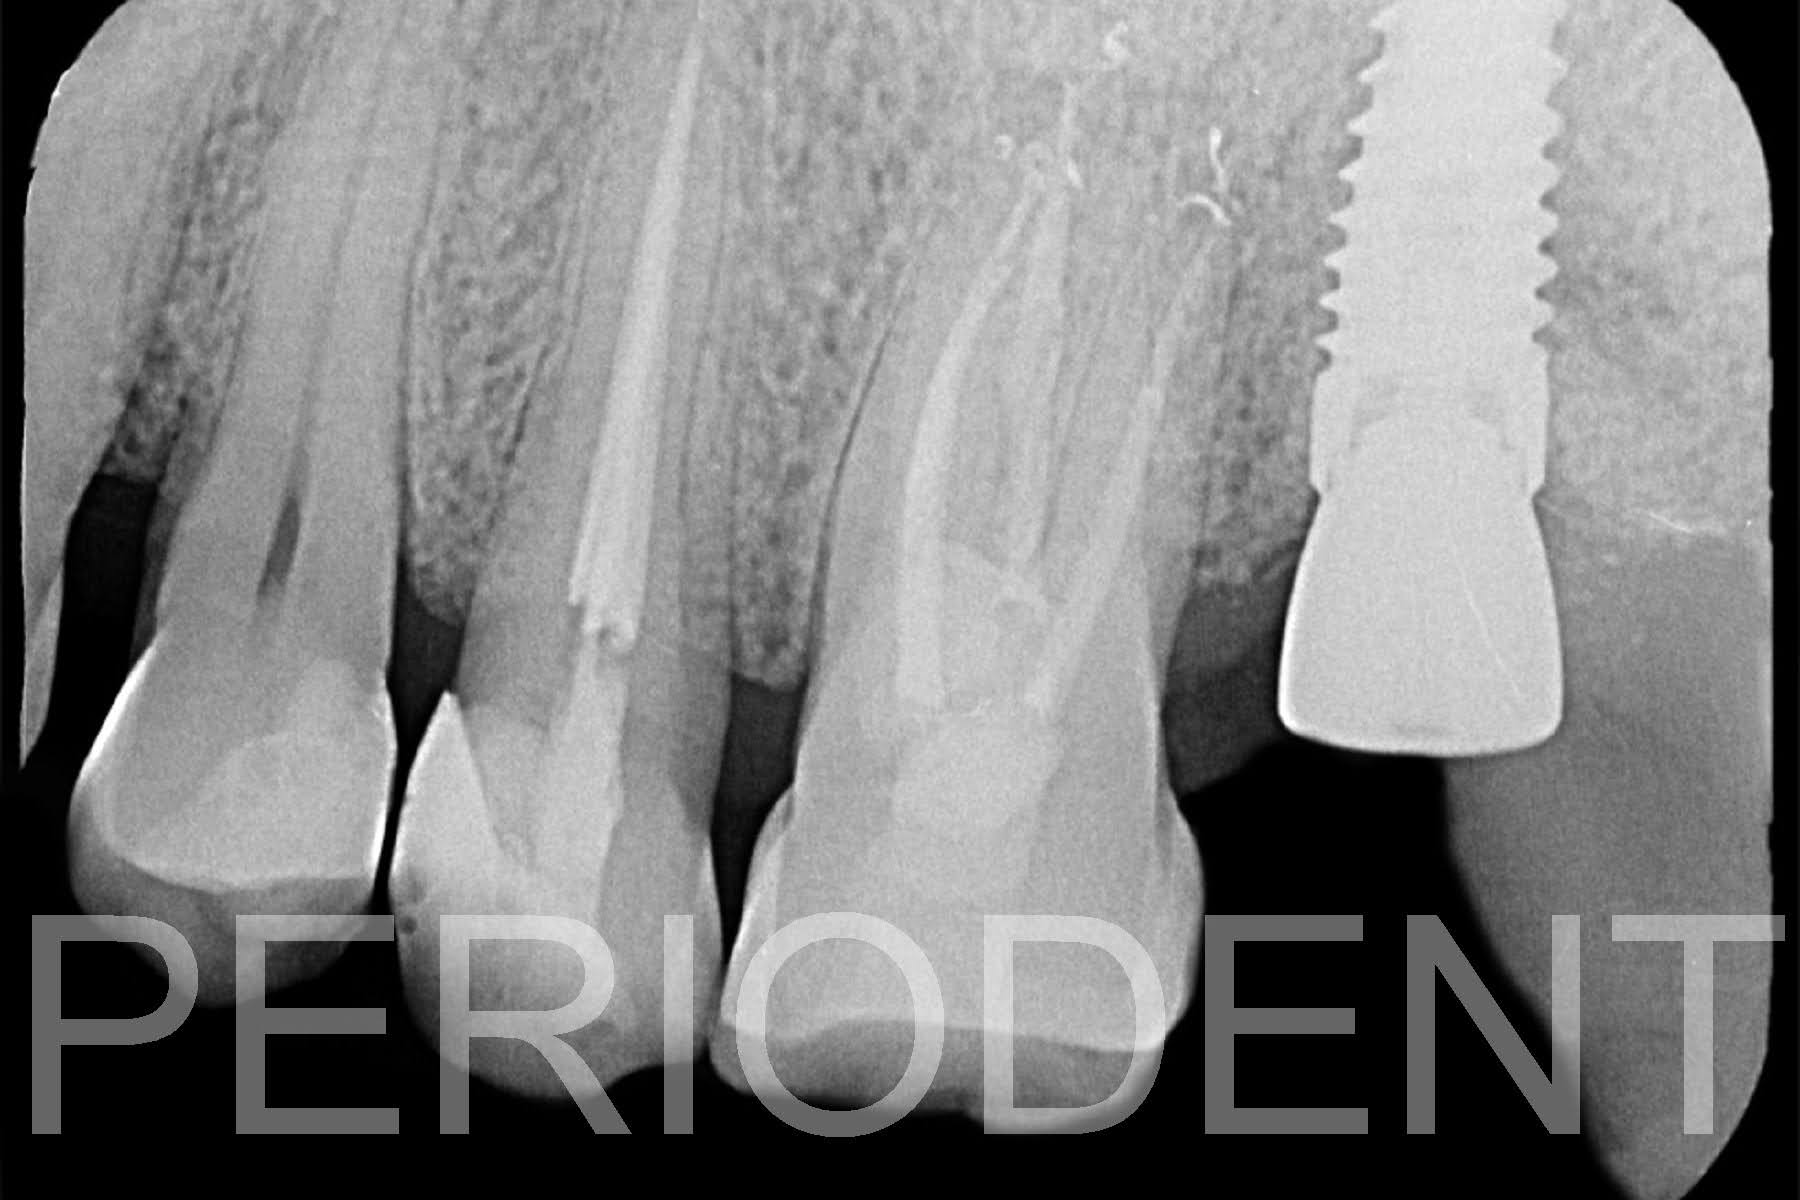

1. 患者在2015年來就診,左上第二大臼齒有嚴重牙周病,牙根上有明顯結石。

經過牙周基本治療後,一年半觀察時。